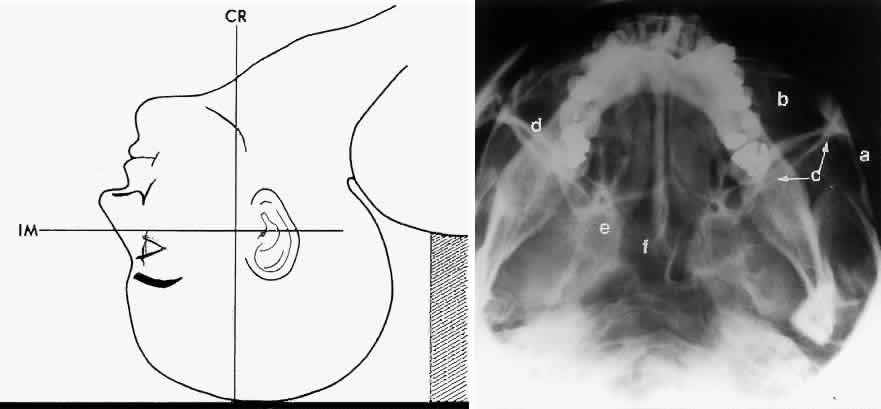

The localization of foreign bodies with plain films is a recurring challenge. Echography and CT have diminished the need for plain film techniques for localization of foreign bodies, but the latter can be used when other imaging modalities are unavailable. Frontal and lateral projections are standard views in these studies (Fig. 18). Localization of a foreign body within the globe is possible with bone-free examination using dental film or by ocular rotation. This latter study localizes the foreign body to either the anterior or posterior segment of the eye. If the foreign body is anterior, the object will rotate in the same direction as the eye. The object will move in an opposite direction to eye movement if its location is in the posterior segment of the eye33 (Fig. 19). Pfeiffer34 and Worst35 used contact lenses as reference devices in localizing foreign bodies. These techniques are less commonly used.

Fig. 19. Foreign body localization using the ocular rotation technique. The patient is directed to look up, as in A, which shows the foreign body moving in the direction of upgaze. B. Foreign body is seen in an inferior location after the patient looked down. This foreign body was located in the anterior segment of the eye.